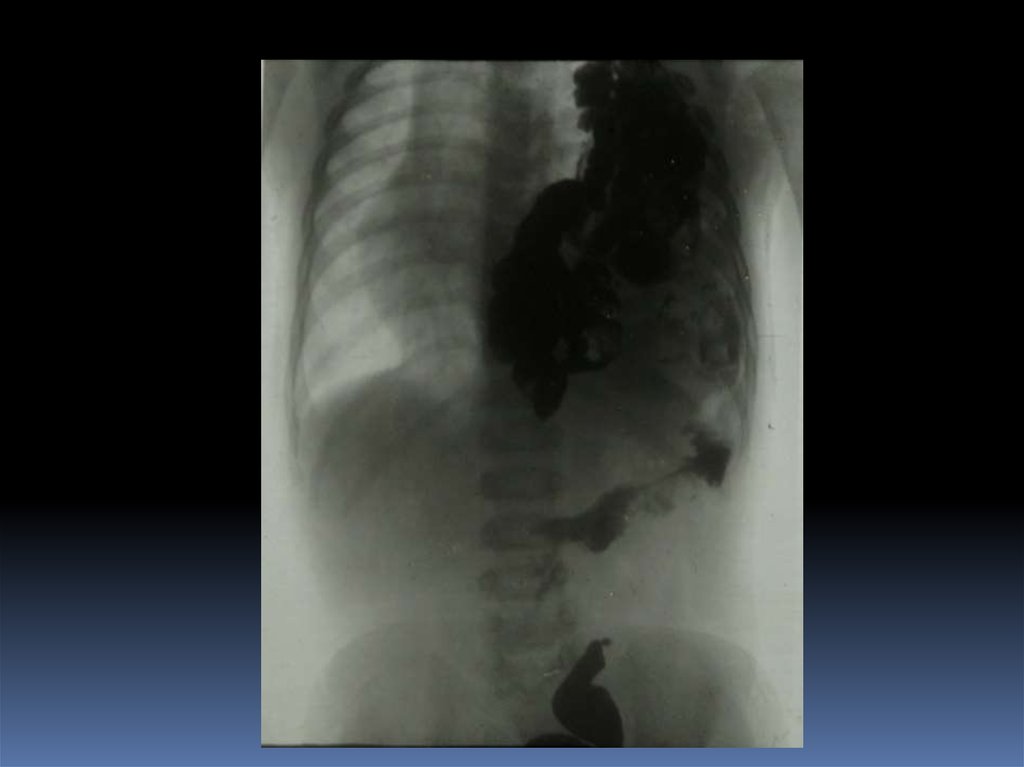

5. Проведение рентгеноскопического исследования раненого.

6. Проведение рентгенографического исследования раненого.

7. Виды травматического повреждения грудной клетки:

пневмоторакс;

гемоторакс;

гемопневмоторакс;

внутрилегочные гематомы;

дисковидные ателектазы;

посттравматические пневмонии.